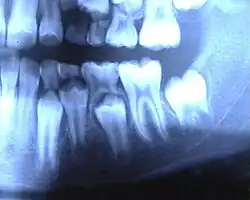

Milchgebiss beim Menschen

Bei einem Kind besteht das Milchgebiss aus 20 Zähnen, und zwar fünf Zähnen pro Quadrant: dem mittleren und dem seitlichen Schneidezahn, dem Eckzahn sowie dem ersten und zweiten Milchmahlzahn. (Das Gebiss wird in vier Quadranten unterteilt: je ein rechter und ein linker Quadrant, jeweils im Ober- und Unterkiefer.)

Der Name erklärt sich einerseits durch die bläulich-weiße Farbe der Milchzähne (d. h., sie sind milchähnlich gefärbt im Gegensatz zum eher gelblichen bleibenden Gebiss), andererseits durch die in der ersten Lebensphase typische Ernährung mit Muttermilch.[2]

Die Milchzähne haben genauso wie die bleibenden Zähne Zahnwurzeln. Die Milchschneide- und Eckzähne haben eine Wurzel, die Milchmolaren haben im Unterkiefer zwei und im Oberkiefer drei Wurzeln. Anomalien sind im Milchgebiss sehr selten. Beim Zahnwechsel mit dem dadurch bedingten normalen Verlust der Milchzähne werden die Milchzahnwurzeln durch die nachdrängenden bleibenden Zähne resorbiert (aufgelöst); die Milchzähne scheinen keine Wurzeln (gehabt) zu haben.